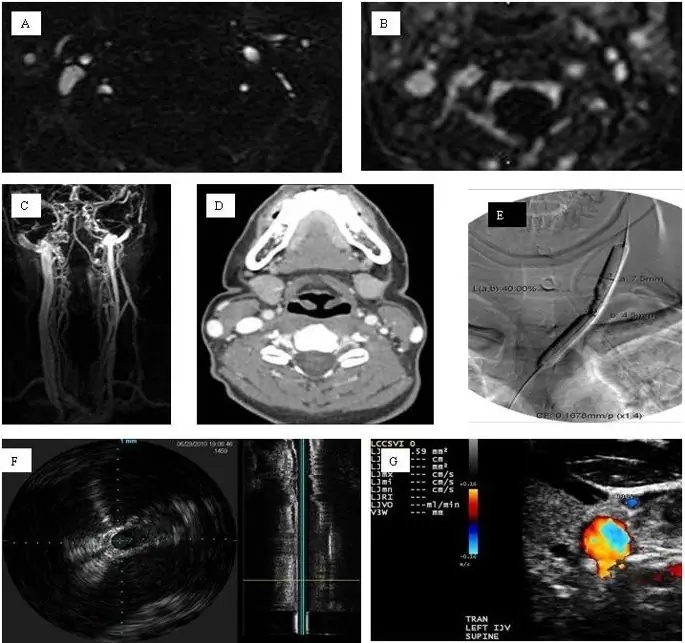

Резкое различие в распространенных результатах между различными исследованиями с использованием неинвазивных и инвазивных методов визуализации (в диапазоне от 0% до 100%) подчеркивает настоятельную необходимость использования мультимодального подхода к визуализации для лучшего понимания рассматриваемых венозных аномалий и вариантов развития в CCSVI (10). В ряде недавних исследований применялись и сравнивались неинвазивные и инвазивные методы визуализации (18, 27, 30, 31, 34, 42, 43, 47), (50, 81, 82, 102, 107, 134). Результаты этих исследований чрезвычайно важны для понимания истинной распространенности CCSVI, и сравнение результатов инвазивной и неинвазивной визуализации особенно важно в этом начинании. Выясняется, что распространенность венозных аномалий и вариантов развития, характерных для CCSVI, еще выше, если исследовать их с помощью сложных методов инвазивной визуализации (47, 107, 108, 134). Основываясь на этих недавних результатах, рекомендуется использовать мультимодальный подход, чтобы определить, существует ли CCSVI как клиническая единица, а не как анатомический вариант, и в какой степени он присутствует в различных здоровых группах и группах заболеваний, а также подтипах РС (рис. 10).). Введение более количественных критериев для описания структурных и гемодинамических нарушений внекраниальной вены в будущих исследованиях по мультимодальному подходу будет значительным улучшением по сравнению с нынешним бинарным диагнозом CCSVI.

figure10

Пример мультимодальной визуализации экстракраниальных вен шеи в исследовании PREMiSe (проспективная рандомизированная эндоваскулярная терапия при РС). Осевое двухмерное время пролета (A), улучшенная трехмерная визуализация с контрастной кинетикой (B и C), доплеровская сонография (D), катетерная венография (E), внутрисосудистая сонография (F) и аксиальная компьютерная томография (G) все венозные аномалии левой внутренней яремной вены (сужение).